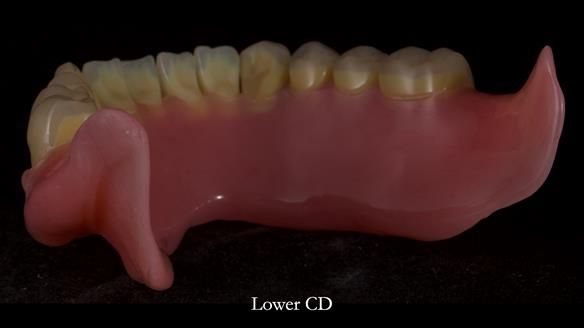

Welcome to Newsletter 83. This month I am sharing Sheila’s case — a very challenging but rewarding complete denture case. Sheila had flat ridges, a small mouth opening, a large tongue and had never been able to wear complete dentures of any kind. Everything was loose and sore. She felt embarrassed and looked older without dentures. She wanted a stable, comfortable result, and she wanted to avoid implants because she has taken bisphosphonates for more than five years.

Because her denture space anatomy was limited, I took two working impressions at the same visit. She had very little space in the lower jaw because of the spread of the tongue and the fact she had never worn a lower denture. This made it difficult to judge exactly where the borders needed to be and how much functional space we truly had.

In Sheila’s case, the Dr Abe shaped impression gave a more stable and comfortable result. Sheila preferred the shape produced by the Abe method, so that is the one we used for the registration rims, the trial denture and the final dentures. But making both impressions was worthwhile. It meant we had every option covered and could choose what worked best for her mouth.

I also want to give a BIG shout out to Rowan, my dental technician. His technical skills are extraordinary, and I could not do this level of work without him. His attention to detail and craftsmanship play a huge part in the success of cases like this.